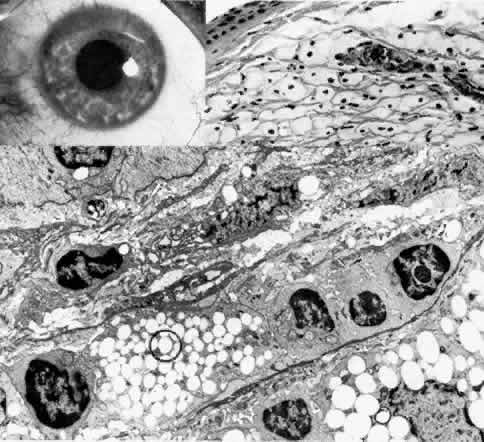

Fleck Dystrophy (Francois-Neetens)

This rare, autosomal dominant dystrophy is detectable very early in life and in some cases is congenital (Fig. 13).161–166 Subtle grayish specks are present in all layers of both corneas, and some appear as rings with relatively less opacified centers. They cause no visual disability. Histopathologic examination has revealed abnormal keratocytes that on transmission electron microscopy show a fibrillogranular substance within intracytoplasmic vacuoles.165 Histochemical staining shows glycosaminoglycans and lipids within these vacuoles.

Fig. 13. Fleck dystrophy (Francois-Neetens). Top left. Artistic representation of discrete, flattened white stromal flecks shows comma, wreath, or dot configuration. Top right. Retroillumination slit lamp photograph demonstrates similar configuration of small, white, granular opacities throughout the stroma. Bottom. Lower right inset is phase-contrast micrograph of a severely affected keratocyte showing foamy cytoplasm with large clear vacuoles (*) and small refractile inclusions (arrowheads) (paraphenylenediamine × 1400). Upper left inset illustrates positive staining for acid mucopolysaccharide limited to a swollen keratocyte (circled) (colloidal iron, × 500). Main figure is transmission electron micrograph of a markedly vacuolated keratocyte filled with fibrillogranular (F) or lipid (L) substances. There are no extracellular abnormalities except an accumulation of the fine granular material (,) and occasional foci of long-spacing collagen (square) (× 12,000). (Nicholson DH, Green WR, Cross HE et al: A clinical and histopathological study of Francois Neetens speckled corneal dystrophy. Am J Ophthalmol 83:554, 1977)